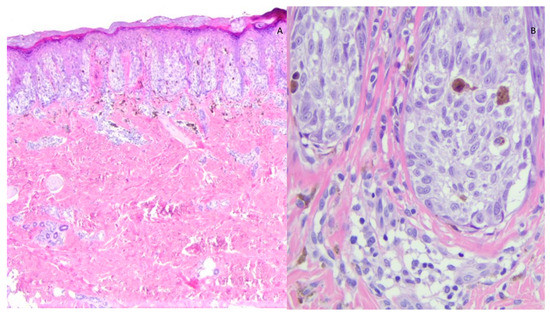

Figure 1.

Histological image of SN showing (A) symmetrical, circumscribed junctional melanocytic proliferation consisting of often vertically oriented nests (raining down appearance) (EE 2×); (B) the junctional nests are composed of elements with spitzoid morphology: large, weakly basophilic cytoplasm and large nucleus with prominent nucleolus (EE 40×).